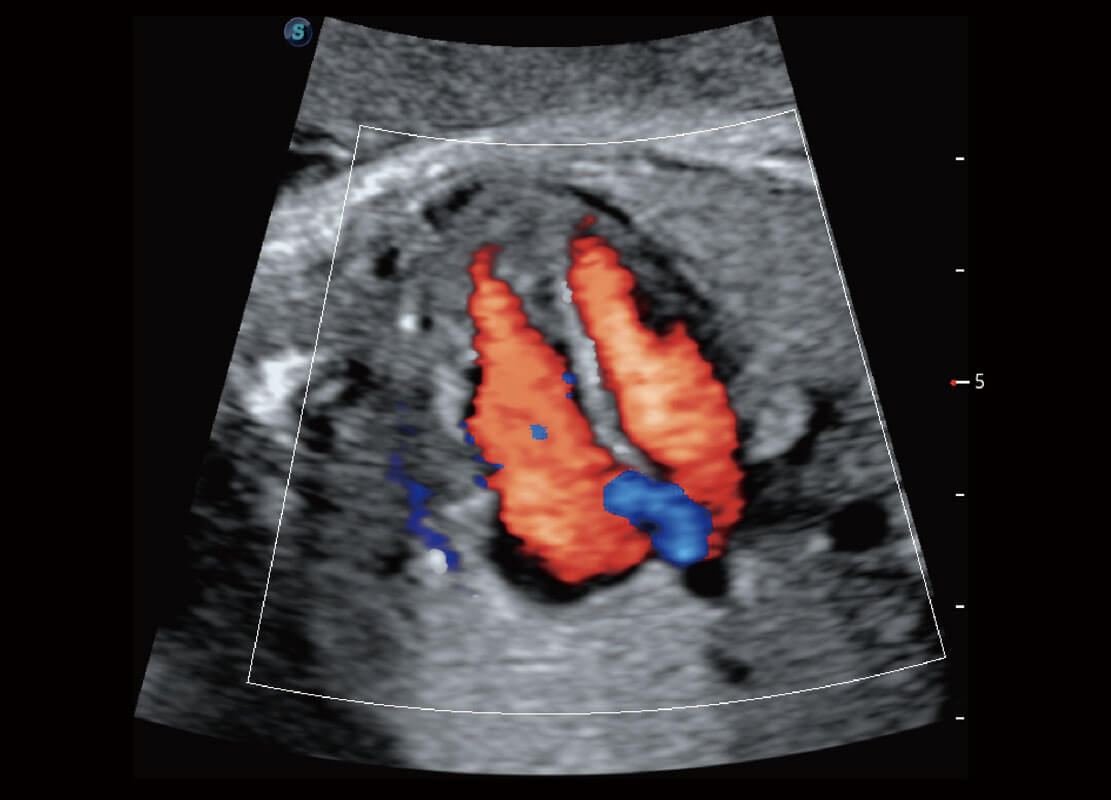

胎儿体循环

早孕-胎心

P60在胎儿早孕期超声筛查中为您带来优异的图像质量。

P60搭载一系列胎儿心脏成像技术,实现精细的胎儿心脏评估。

四腔心血流